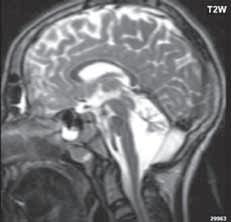

I.1.7 Chiariho malformace (ArnoldovaChiariho malformace)

Rozlišujeme tři formy (typy) této malformace. Chiari I je charakterizován sestoupením mozečkových tonzil do foramen okcipitale magnum do oblasti krční páteře (u dospělých jsou tonzily mozečku max. 5 mm pod úrovní baze lební, u malých dětí (do 10 roků) do 6 mm. Tonzily bývají na podélném řezu přirovnávány ke klínům, které jako by byly zatlučeny do týlního otvoru „pek like“. Chiari II malformace je ve 100 % doprovázena otevřeným spinálním dysrafismem (obvykle myelomeningokélou). Chiari III lze definovat jako Chiari II + okcipitální nebo cervikální encefalomeningokéla. Chiari IV, kde je navíc přítomna hypoplazie mozečku, do této skupiny nezařazujeme, vývojově patří do poruch ventrální indukce.

Zobrazení

Chiari I: CT a MR zobrazí malou zadní jámu lební, absenci cisteren zadní jámy lební, pokles tonzil, krátký a konkávní klivus, poruchu cirkulace mozkomíšního moku v oblasti foramen magnum a následný hydrocefalus. MR navíc může prokázat edém krční míchy a ve vysokém procentu případů hydrosyringomyelii.

Chiari II: CT a MR zobrazí malou zadní jámu lební, absenci nebo výraznou redukci cisterny cerebelomedulární a dalších kmenových cisteren, konkávní klivus. Mohou být abnormality v oblasti foramen okcipitale magnum, nízký úpon tentoria, někdy absence nebo fenestrace falx cerebri. MR lépe ukáže kaudálně uloženou a protáhlou IV. komoru (někdy je přirovnávána až ke stéblu slámy), protažený pons a další možné, přidružené abnormality (hydrosyringomyelii, agenezi, hypogenezi nebo fenestraci corpus callosum…).

Prenatální sonografie: Spinální dysrafismus se obvykle diagnostikuje v 20.–22. týdnu, podezření může být vysloveno již v prvním screenigovém období (11.–13. týden). V screeningovém období 20.–22. týdne lze diagnostikovat Chiariho malformaci: je patrný příznak „banánu“ –

mozeček je posunut dorzálně a tvoří konvexní strukturu a příznak „citrónu“, který vytváří symetricky vkleslé části lebky frontálně.

Chiari III: Chiari II + okcipitální nebo cervikální encefalomeningokéla.

Diagnostika a klinický obraz

Chiari I malformace je v 50 % asymptomatická, u symptomatické skupiny pozorujeme bolesti hlavy a krční páteře, tortikolis, mozečkové symptomy. Existují i nemocní se závažnými příznaky komprese mozkového kmene, se záchvaty drop atak (náhlá porucha funkce posturálních svalů spojená s pádem bez poruchy vědomí), mohou končit i náhlou smrtí. Léčba je chirurgická dekomprese v subokcipitální oblasti, snahou je zajistit normální cirkulaci likvoru (u asymptomatických pacientů se operační dekomprese nedoporučuje, neboť má pochopitelně řadu komplikací).

U Chiari II malformace je klinický obraz ovlivněn myelomeningokélou, bývá přítomna paraparéza DK, poruchy sfinkterů, při dekompenzaci hydrocefalu, se mohou objevit kmenové příznaky. Léčbou je řešení spinálního dysrafismu, hydrocefalu (obnova normální cirkulace likvoru), dekomprese v subokcipitální oblasti.

Obr. I.1.7a Sestup mozečkových tonzil (šipka), Chiariho malformace I

Obr. I.1.7b Sestup mozečkových tonzil, „pek like“ (šipka), Chiariho malformace I c d

Sestup mozečkových tonzil,

Myelomeningokéla